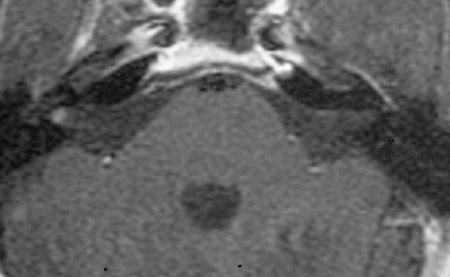

The diagnosis of vestibular schwannoma is made by history, hearing tests, and MRI scan. Gadolinium is a special contrast agent used during the MRI to allow visualization of the tumors. With good technique, MRI will show tumors as small as 2-4 millimeters.

MRI showing 2mm vestibular schwannoma in right internal auditory canal